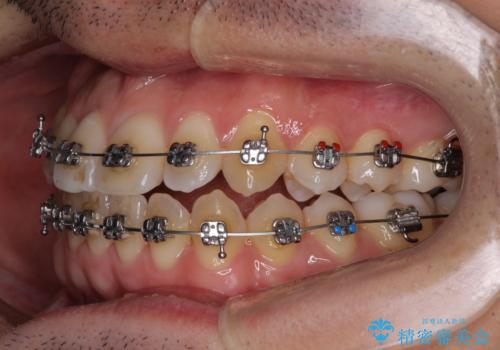

- 矯正装置

- メタルブラケット

舌の突出癖がなかなか改善されず、上下前歯部の接触が得られるまでに予定の倍ほどの期間がかかりました。